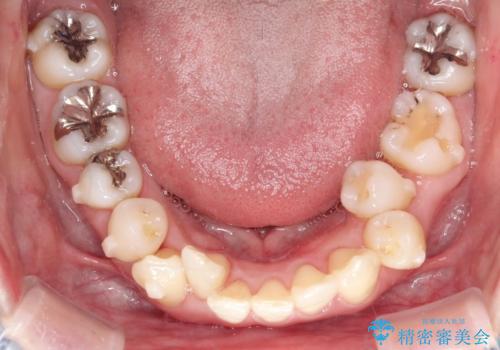

上下のガタガタのマウスピースによる非抜歯矯正

- 上下のがたつきを主訴に来院された患者様です。

上下の前歯と奥歯にがたつきがありました。

上下の奥歯を後方に移動させるのと、歯と歯の間をわずかに削ることでスペースを作り、歯を並べる計画としました。

比較的がたがたの度合いが大きかったですが、しっかりとマウスピースを使用していただけたので、順調に治療を終えることができました。